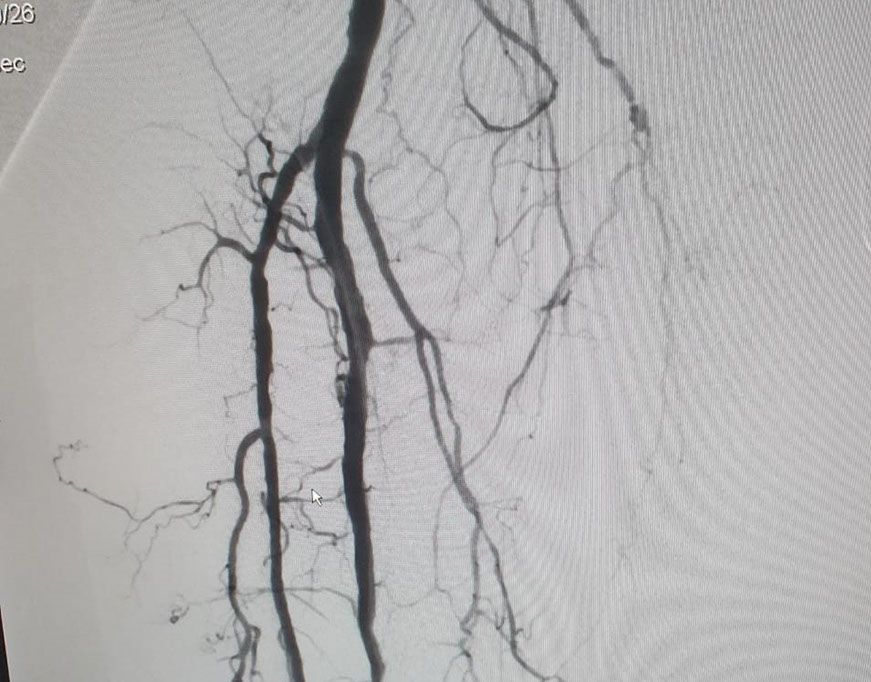

El Dr Sergio Raul Ludueña Jefe del Servicio de Hemodinamia de INCOR nos comentó sobre procedimiento realizado en el día de ayer en en el Servicio. "Queremos compartir con ustedes si bien no es un caso coronario , es un paciente obeso mórbido, diabético, con amputación supracondilea de miembro inferior izquierdo hace 3 años y actualmente con isquemia critica de miembro inferior derecho, con oclusión de ambas tíbiales y sin circulación en el pie".

Se realizó un abordaje híbrido con el Dr. Alejandro Flores, y se re canalizó ambas arterias tíbiales. Procedimiento inédito en nuestra provincia.

Las imágenes siguientes son previas al procedimiento y posterior se ve ambas arterias tíbiales permeables, y circulación en el pie

El procedimiento lo realizo el equipo de Hemodinamia de INCOR dirigido por el Dr. Ludueña junto con la intervención del Dr. Alejandro Flores (Flébologo y cirujano vascular)